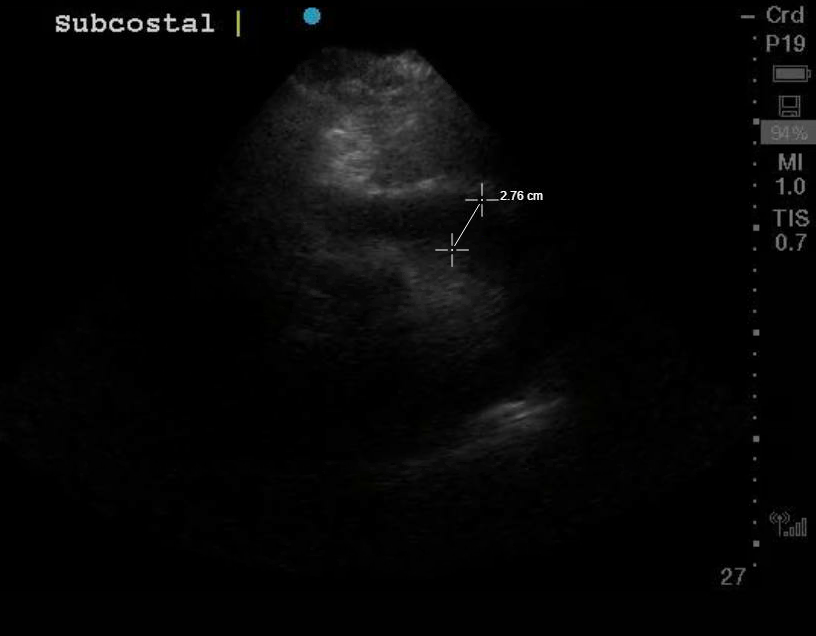

A 72 year old female presented to the ED with chest pain. Dr. Scavelli took the ultrasound and performed a cardiac POCUS and saved clips/images which showed this:

The patient had just had an echo very recently that had NO pericardial effusion. The clip demonstrates a large circumferential pericardial effusion in a parasternal short view. The heart looks like its floating in fluid.

Dr. Scavelli noted that the patient was hypotensive and given the POCUS had a pericardial effusion which equated to possible tamponade, he immediately called CT surgery who agreed with his assessment. The patient went to the OR and had 550cc of bloody pericardial fluid drained.